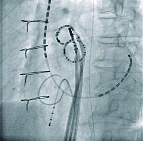

肺静脈隔離治療・透視画像

左前斜位

X線透視画像を確認しながら、医師はカテーテル治療を行う

足の付け根の静脈や首の静脈からX線透視画像を確認しながらカテーテルを心臓まで挿入し、心臓内に数本の電極カテーテルを留置します。この電極カテーテルから得られる電気の流れなどを確認しながら、アブレーションを行っていきます。実際に記録される電位に加えて、胸部に貼ったパッチと心房内のリングカテーテルから位置情報をとり、モニターに心房を中心とした三次元のカラーマッピング画像を描出します。図は肺静脈隔離術後の左心房の三次元マッピングですが、焼灼を終えた低電位領域は赤、高電位領域は紫で表示され、肺静脈の隔離が改めて確認できるのです。